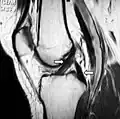

Magnetic resonance imaging evaluation demonstrating normal signal of both anterior and posterior cruciate ligaments (arrows). -